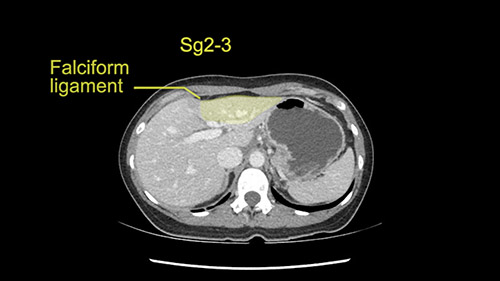

So if we look at the CT scan, on the axial, it’s a larger lesion. It’s about 6 or 7 or 8 centimeters. So it does look a bit threatening in terms of its resectability but if you really drill down deeply into the anatomy, and I think the coronal [imaging] is even better, you can see that the entire mass is on the patient’s left side of the falciform ligament. So it’s really only a left-sided tumor and not even really a left-sided tumor because Segment 4 is uninvolved anatomically.

As I review the CT scan, we have both arterial and venous phases, the tumor is obvious. But I’ll start by saying that the liver itself does not appear to be cirrhotic to my eye. It’s got a normal contour and allied to that, that I do not see evidence of portal hypertension. The spleen is normal, there’s no collateral vessels. The tumor itself, I measured maximally at about 11 centimetres in diameter and I’m told the alpha fetoprotein is very high (over 10000), which is entirely consistent with this being a solitary hepatocellular carcinoma that is very exophytic. It seems to emanate off the inferior margin of Segment 3 (because that’s the falciform). I’ll start by saying that this is not transplantable. The tumor exceeds our guidelines for transplantation, but it's likely resectable based on normal liver and no portal hypertension.

So the issue with regards to resection. A left sided tumor. I believe I can see the falciform ligament right here so we’re looking at a resection of Segments 2, 3 of the left lobe of the liver. The left portal vein is right there. I think we’ll be wiser to take the left portal vein and therefore get well into Segment 4 and do a left hemihepatectomy. Certainly, one does not need to take the middle hepatic vein; it’s miles from the tumor.

What kind of procedure can we plan for this patient? It obviously has to be a left hemihepatectomy because most of the lesion is actually in Sg4. Can we do something which is less than a hemihepatectomy and just do only a segmental resection? The answer to that is that this vascular supply, if you are trying to ligate only the portal venous pedicle to the Segment 4, it is very close to the tumor and you will end up not having not a great margin as far as tumor resection is concerned so I would recommend a left hemihepatectomy and not just a partial or segmental resection. You can also see that it is crossing the falciform line and going on to Segment 2 and 3 so trying to do anything less than a left hemihepatectomy may not give the right kind of margins which we need for this tumor. Fortunately for us, the contours of the liver, which are very important to see in a Hepatitis B patient, there are no cirrhosis which I can see. The normal liver functions indicate that it's a well compensated Hepatitis B.

The other thing I would do in this case is to certainly to assess the coronal phase as we can see in the coronal phase, this tumor looks like it's growing from Segment 3, and again I don’t think there’s involvement of the right side of the liver or even on Segment 4.